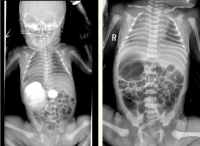

“镜面宝宝”出生即遇肠梗阻,妇幼多学科联手成功施救

“孩子终于脱离危险了!”看着病床上逐渐平稳的宝宝,宝鸡市民李先生(化名)夫妇悬了许久的心终于放下。这个特殊的宝宝是罕见的“镜面人”,出生即因十二指肠梗阻频发呕吐,宝鸡市妇幼保健院多学科团队联手施救,成功为孩子“打通”肠道,创造了生命奇迹。